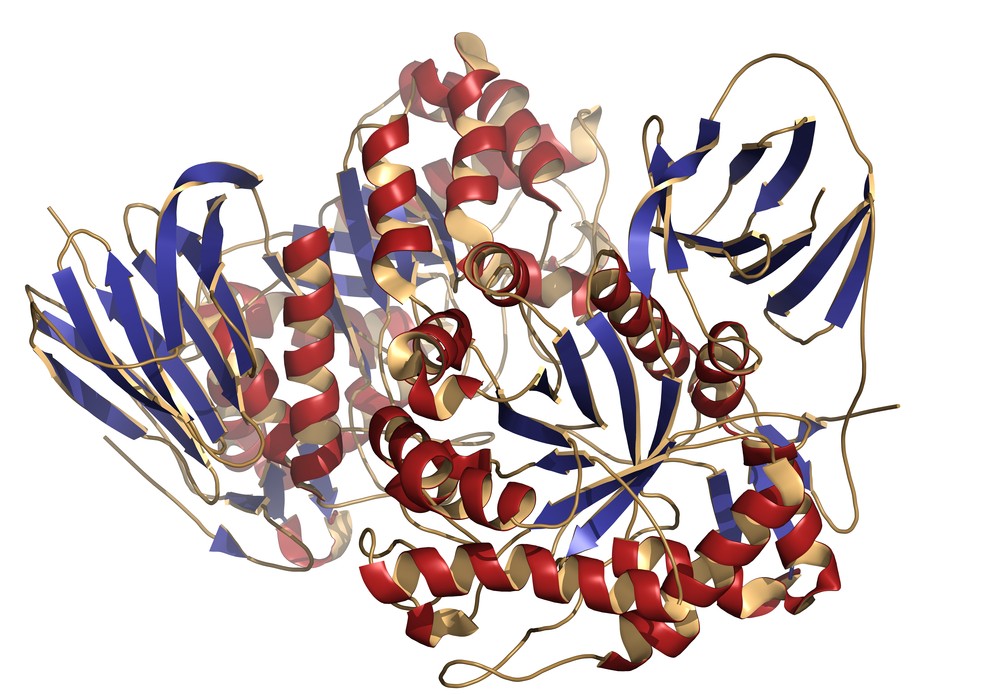

Israeli scientists offer new hope for Gaucher patients

Weizmann Institute of Science researchers have discovered a new cellular pathway implicated in Gaucher disease.

Weizmann Institute of Science researchers have discovered a new cellular pathway implicated in Gaucher disease.